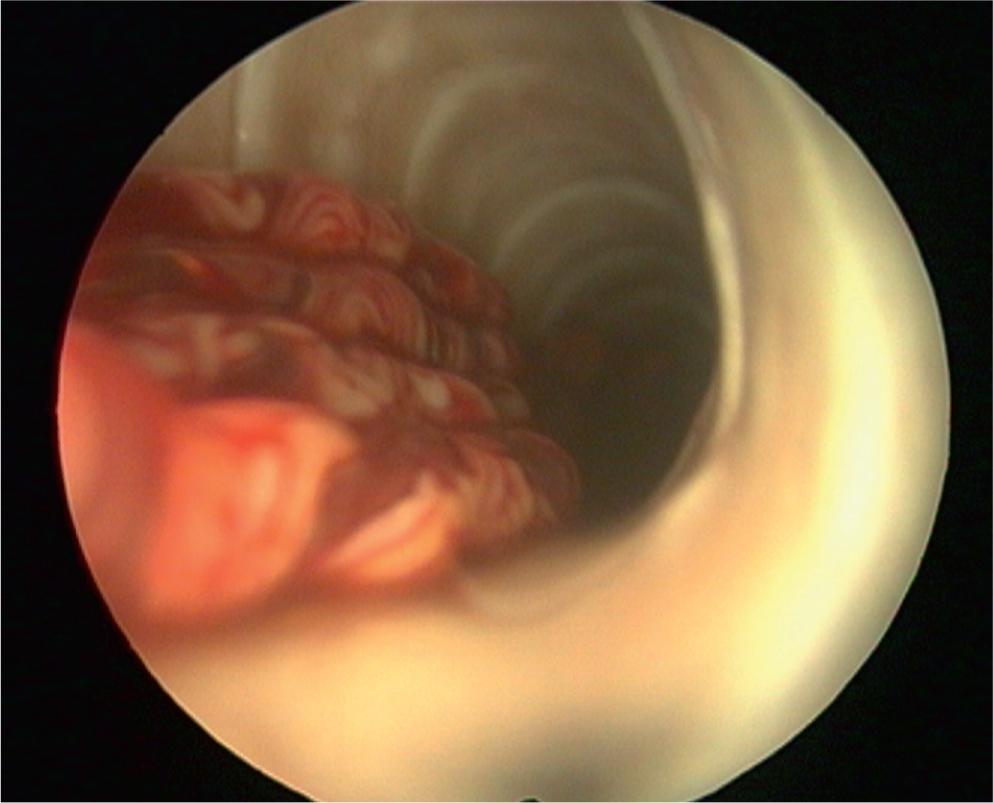

A parasitological necropsy of a bird involves a detailed post-mortem examination to identify internal and external parasites. In short, the process begins with external examination for lesions or discharges, followed by incisions to the body cavity to assess internal organs, air sacs, and the gastrointestinal tract for parasites, abnormalities, and changes in tissue consistency, size, or color. Samples of organs and contents are collected for further analysis, including microscopic examination for parasites (Van Riper, 1980). Figures 1 – 2 show the trachea in situ, highlighting the presence of S. trachea within its structure. Figure 3 illustrates infectious larvae L3 encysted in the earthworm’s body wall.

Tracheoscopic finding of Syngamus trachea adults fixed to tracheal mucosal lining.

Short-term inhalant anesthesia with isoflurane was applied to the birds in individual groups to examine the trachea. Tracheoscopy to the level of the syrinx was possible in medium- to large-sized birds using a 180 mm long, 2.7 mm endoscope. Visualization could be improved by extending the pheasant neck (Murray et al., 1999). Simultaneously, the blood was withdrawn from the jugular vein.